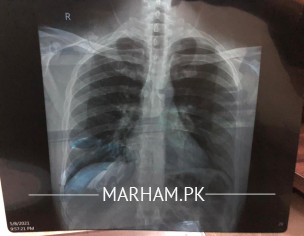

I am 32 years old pcr test in negative but i am having heavy chest ,tmp and boday aches. My cheat x ray is attached plz tell me is it clear or not

minute opacities B/L

It is normal..

U need get check up for ur symptoms